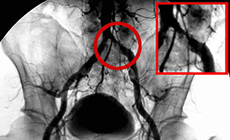

狭心症、心筋梗塞、末梢動脈疾患が疑われる患者さまがいらっしゃいましたら、循環器内科外来あてにご紹介ください。

循環器専門の医師が患者さまを診察し、適切な検査計画を検討させていただきます。